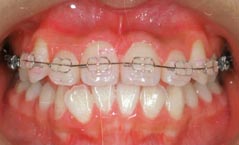

治療前

治療後